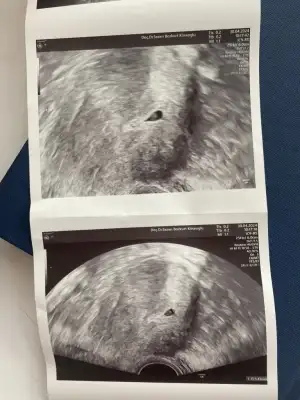

merhaba kızlar bu ilk sohbetim olacak 😊 sürekli yazılanları okuyorum içim biraz olsun rahatlıyor. Doktorlar daha ayrıntılı bilgiyi buradan alıyorum kafam rahatlıyor. Geçen sene 30 nisanda dış gebelik geçirdim iğneyle sonlandırdılar sol tüpümdeymiş tüpü aldırmadım. Normal hamile kalabileceğimi söylediler şansımı denemek istedim. Ve çok şükür 24 nisan da test yaptım hamile olduğumu öğrendim (5+1) cuma günü kan verdim betam 1439 çıktı pazartesi yine verdim 2493 çıktı salı günü özele gittim alttan muayene oldum kese göründü yolk sac göründü ama kesem damla şeklindeymiş ( aşağı fotosunu atıcam) aynı gün akşamı devlette başka bir doktora gittim o da kesemde bir sorun olmadığını sağlıklı olduğunu haftaya gel büyüme var mı bakalım dedi. İçim huzurlu iyi şeyler duyucam sağlıklı bir bebek alıcam kucağıma 🤲🏻🧿😍 buna inanıyorum. Görünmediyseniz ikinci hatta üçüncü bir doktora görünmenizde fayda var 😊 umarım hepimiz sağlıkla alırız minnoşları kucaklarımıza 🤲🏻